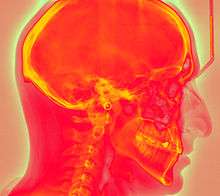

Computed radiography (CR) uses very similar equipment to conventional radiography except that in place of a film to create the image, an imaging plate (IP) made of photostimulable phosphor is used. The imaging plate is housed in a special cassette and placed under the body part or object to be examined and the x-ray exposure is made. Hence, instead of taking an exposed film into a darkroom for developing in chemical tanks or an automatic film processor, the imaging plate is run through a special laser scanner, or CR reader, that reads and digitizes the image. The digital image can then be viewed and enhanced using software that has functions very similar to other conventional digital image-processing software, such as contrast, brightness, filtration and zoom.

Computed radiography (CR) is often distinguished from Direct Radiography (DR). CR and DR have many similarities. Both CR and DR use a medium to capture x-ray energy and both produce a digital image that can be enhanced for soft copy diagnosis or further review. Both CR and DR can also present an image within seconds of exposure. CR generally involves the use of a cassette that houses the imaging plate similar to traditional film-screen systems, whereas DR typically captures the image directly onto a flat panel detector without the use of a cassette. Image processing or enhancement can be applied on DR images as well as CR images due to the digital format of each. There are many different types of DR detectors in use in medicine and industry. Each type has its own merits and distinctions and may be applied to certain imaging requirements based on these attributes.